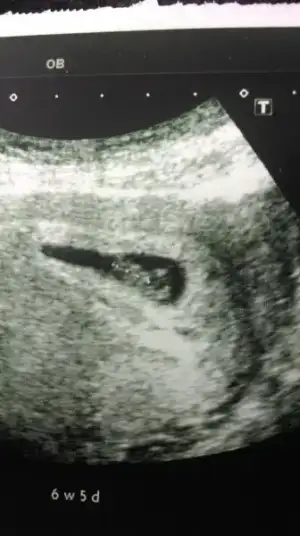

Kizlar bu da benim ultrason sonucum. Sata gore tam 7 hafta ultrasona gore 6 haftaligiz. Kalp atisi duyulmadi henuz. Kesenin sekli cok duzgun cok bicimli guzel bir gebelik kanaman yok dedi doktorum. 2 hafta sonra gel kalp atisi icin dedi. Kalp atisini duymamamiz normal mi dedim. Tabi normal daha kucuk kesen gec olusmus dedi. Hadi bakalim hayirlisi olsun hepimiz icin.